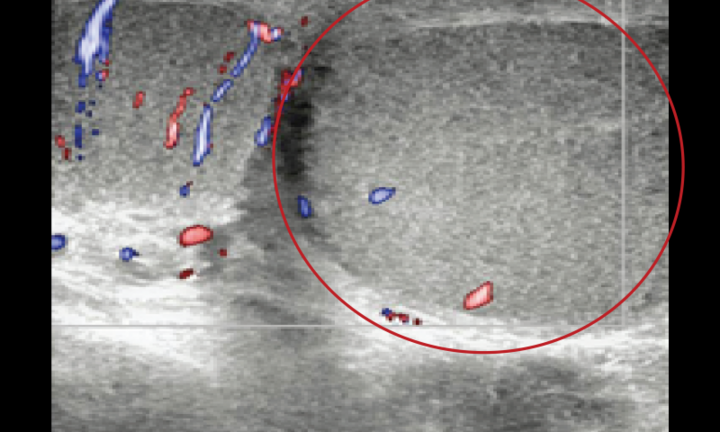

Dị vật là viên pin điện tử hình cúc áo có đường kính 20mm được gắp ra ngoài thành công, kiểm tra tại vị trí viên pin mắc lại đã có hiện tượng bỏng thực quản. Các bác sĩ cho biết, khác với những dị vật vô cơ khác, trường hợp dị vật là viên pin mắc lại thực quản, nếu không được can thiệp sớm sẽ gây ra một loạt các biến chứng nguy hiểm vì khi viên pin nằm lại ở thực quản vẫn còn hoạt động và có hiện tượng kiềm hóa xảy ra ở cực âm, dẫn tới bỏng hóa chất kiềm tại thực quản.